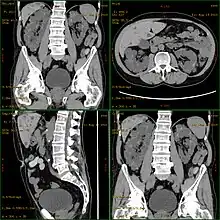

CT scan showing autosomal dominant polycystic kidney disease

Autosomal dominant polycystic kidney disease (ADPKD) is the most common of all the inherited cystic kidney diseases[12][13][14] with an incidence of 1:500 live births.[12][14] Studies show that 10% of end-stage kidney disease (ESKD) patients being treated with dialysis in Europe and the U.S. were initially diagnosed and treated for ADPKD.[12][11]